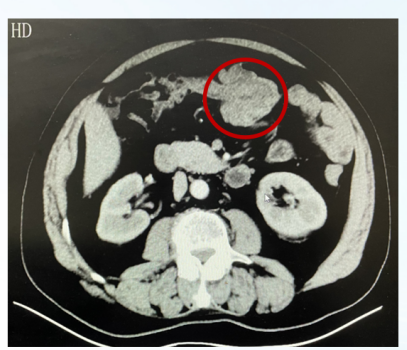

影像学检查:

胸部+全腹部增强CT(2017-10):1、降结肠及乙状结肠交界处增厚,多为肿瘤,建议活检;结肠部分梗阻;2、双肾囊肿;3、盆腔少许积液;4、前列腺增生并钙化;5、腹主动脉钙化;胸腰椎退行性变。

图1、患者腹部增强CT(2017-10)